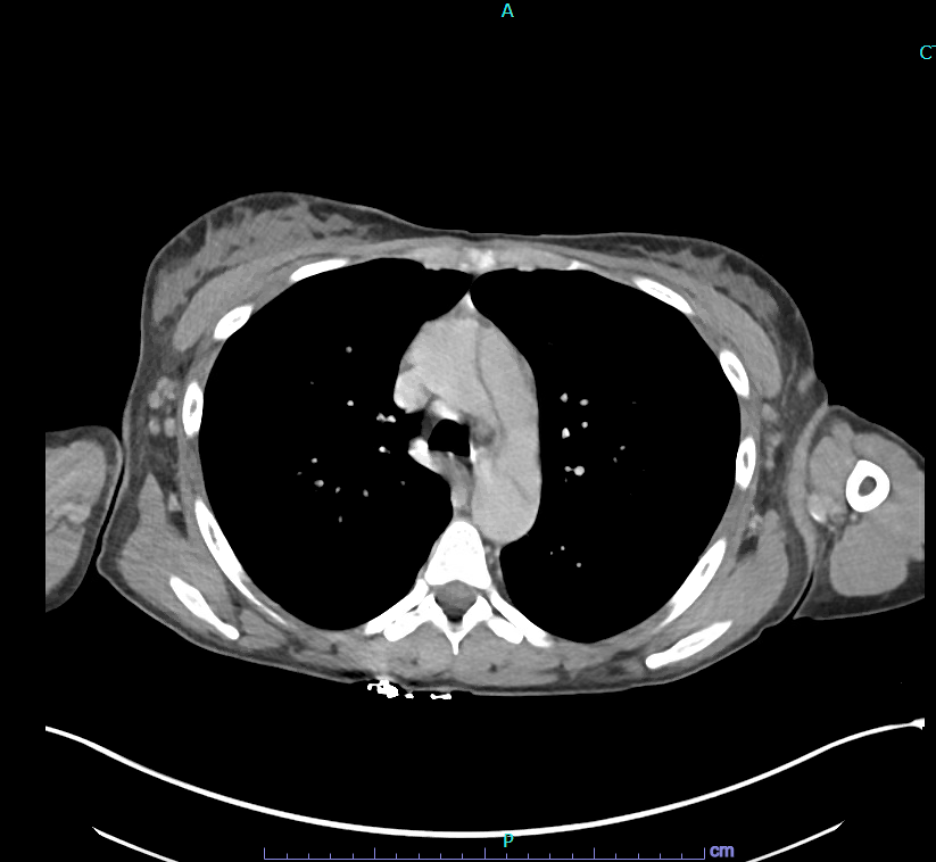

An elevated erythrocyte sedimentation rate (ESR) of 60 mm/hour was also noted (normal level, > 20 mm/hour for women younger than 50 years of age), indicating underlying inflammation. Computed tomography angiography (CTA) confirmed the diagnosis of a Stanford Type A aortic dissection (AD), extending from the root of the aorta to the bilateral external iliac arteries. A transesophageal echocardiogram (TEE) was performed, which provided additional detail regarding the extent of the dissection and its effect on the aortic valve. Laboratory tests revealed a hemoglobin level of 7.5 g/dL (normal range, 12-16 g/dL in women, 13.5-17.5 g/dL in men), elevated C-reactive protein (CRP) of 31 mg/L (normal range, < 5 mg/L), and serological markers consistent with active SLE. These include positive anti-nuclear antibody, anti-double stranded DNA antibodies, and low complement levels C3–36 (normal range, 90-180 mg/dL), C4–13 (normal: 10-40 mg/dL). The combination of imaging studies and laboratory findings allowed for a comprehensive assessment of the patient’s condition, facilitating prompt diagnosis and initiation of appropriate treatment measures1.

Figure 1. Computed tomography angiography (CTA) showing aortic dissection in a patient with systemic lupus erythematosus (SLE).